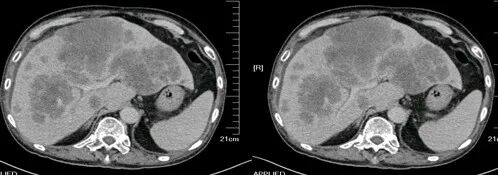

胃癌

进展期胃癌CT检查有利于观察病变的侵犯范围和淋巴结转移情况

升结肠癌并广泛转移

升结肠癌并肝转移